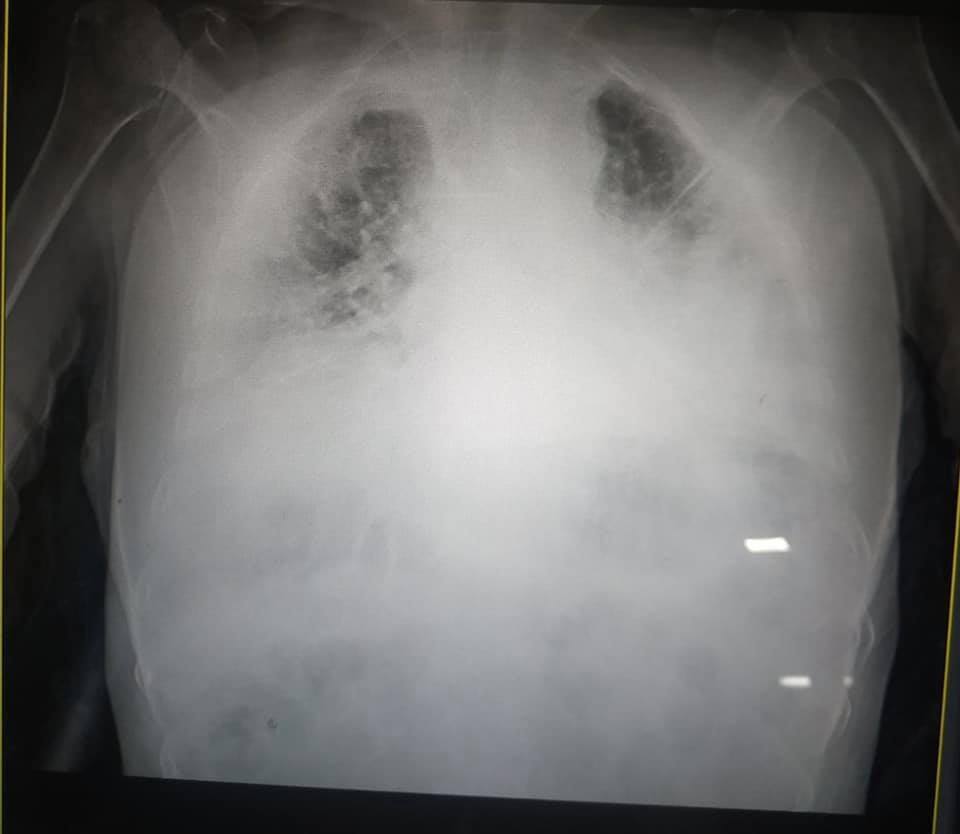

Врач показала "самые страшные" легкие больного COVID-19

Украинская журналистка Ирина Заславец показала фото рентгена легких, пораженных коронавирусной болезнью (COVID-19).

Снимки она опубликовала в Facebook после общения с главой реанимации Клинической больницы скорой медицинской помощи Львова Натальей Матолинец.

"Это одни из самых страшных легких, которые я видела в жизни", – отметила врач.

Заславец добавила, что ранее из Винников в областную больницу доставили 18 пациентов с COVID-19, 7 из них – в реанимации. Все в критическом состоянии, подчеркнула журналист.